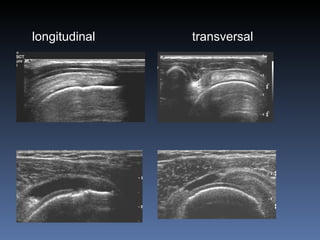

Ultrasonido Relativamente barato Las ondas de sonido son reflejadas en las interfaces de los tejidos blandos  No da radiacion ionizante Aplicaciones en Musculo-esqueletico En niños para Displasia/luxación de cadera Lesión de tendones como en el manguito rotator Masas de tejidos blandos Toma de biopsia guiada por ultrasonido

longitudinal transversal

Ultrasonido Relativamente baratoLas ondas de sonido son reflejadas en las interfaces de los tejidos blandos No da radiacion ionizante Aplicaciones en Musculo-esqueletico En niños para Displasia/luxación de cadera Lesión de tendones como en el manguito rotator Masas de tejidos blandos Toma de biopsia guiada por ultrasonido